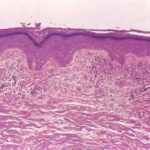

The variable epidermis may be hyperkeratotic with focal parakeratosis, acanthotic to atrophic, and with focal spongiosis. There is proliferation of small blood vessels in the papillary dermis, forming lobular aggregates {glomeruloid proliferation}. The proliferation may be florid, mimicking Kaposi’s sarcoma {acroangiodermatitis} . There is a superficial perivascular lymphocytic infiltrate that surrounds thickened capillaries and venules. The reticular dermis is often fibrotic. Extravasated erythrocytes and hemosiderin are usually present superficially, but they may be identified about the deep vascular plexus as well. Fibrin thrombi may be observed in the small vessels, likely reflecting flow disruption and anoxia. They do not indicate a concurrent coagulopathy. Endothelial necrosis and neutrophils may be present as well, reflecting similar changes, and do not indicate a leukocytoclastic vasculitis